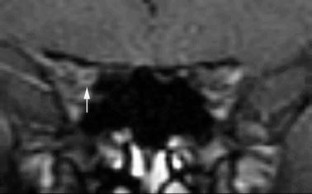

Optic nerve sheath dilatation or gadolinium-enhancement on magnetic resonance imaging in acute optic neuritis have been previously reported but have been thought to be rare occurrences. This study recruited 33 patients with acute unilateral optic neuritis. All had their optic nerves imaged with fat-saturated fast spin-echo (FSE) imaging, and 28 had imaging before and after triple-dose gadolinium-enhanced fat-saturated T1-weighted imaging. Follow-up imaging was performed on 20 patients (15 following gadolinium). A dilated subarachnoid space at the anterior end of the symptomatic optic nerve on FSE imaging was seen in 15/33 cases. In three of these cases, dilatation was visible on short-term follow-up. Optic nerve sheath enhancement was seen in 21/28 cases acutely: seven at the anterior end of the lesion only, five at the posterior end only and nine at both ends. Optic sheath enhancement was seen in 13 patients on follow-up. This study suggests that optic nerve sheath dilatation on FSE images and optic nerve sheath enhancement on triple-dose gadolinium-enhanced images are common findings in acute optic neuritis. Optic nerve sheath dilatation may be due to inflammation of the optic nerve, with its associated swelling, interrupting the communication between the subarachnoid space of the diseased optic nerve and the chiasmal cistern. Optic nerve sheath enhancement suggests that meningeal inflammation occurs in optic neuritis, in agreement with pathological studies of both optic neuritis and multiple sclerosis.